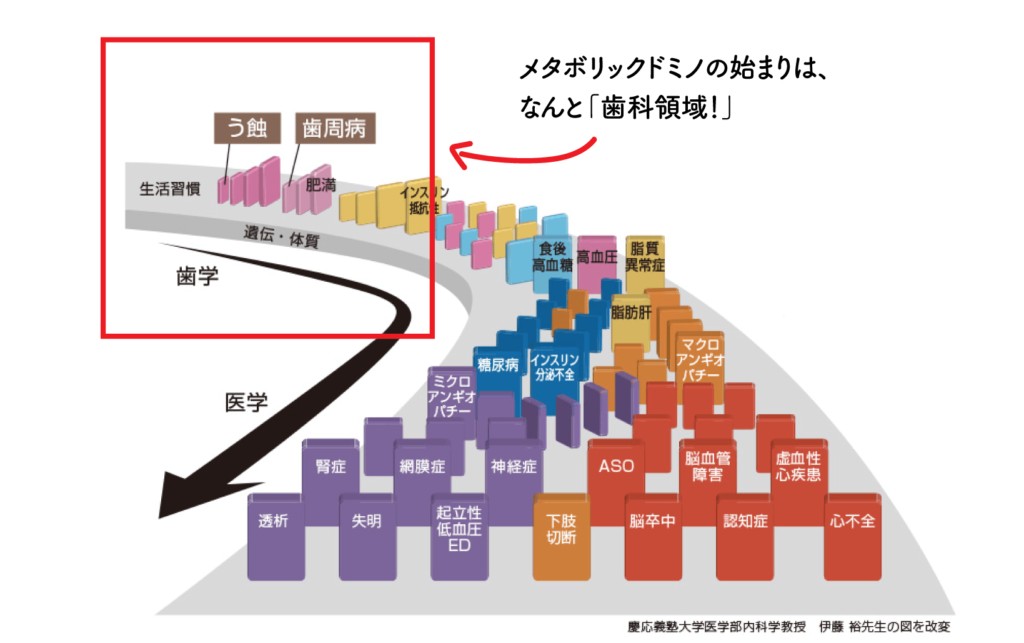

慢性炎症が放置されると…ドミノ倒しのように進行

慢性炎症を放置すると、全身の健康に深刻な影響が現れます。例えば、

動脈硬化:血管壁が炎症を起こし、血栓ができやすくなる

糖代謝異常:インスリンの働きが悪化し、血糖値のコントロールが難しくなる

これらが進行すると、最終的に糖尿病、心筋梗塞、脳梗塞、腎臓病、認知症など、重大な病気に連鎖的につながる可能性があります。

これは「メタボリックドミノ」と呼ばれ、ひとつの炎症が連鎖的に他の病気を引き起こすのです。

虫歯や歯周病も「慢性炎症」!?

意外かもしれませんが、「虫歯」や「歯周病」も慢性炎症の一種です。メタボリックドミノの図をみてもわかる通り、大元の生活習慣、つまり「何を食べてどうケアしているか」に辿り着きます。